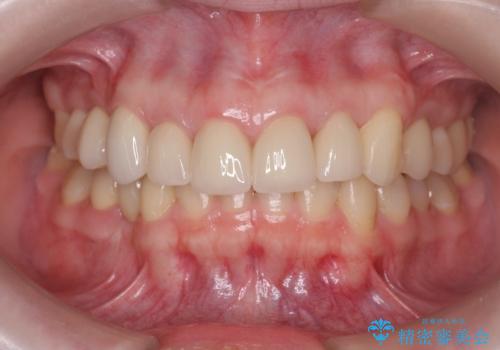

多発した前歯の重度虫歯治療

- 放置した虫歯の歯がボロボロになってしまい治療を希望され来院されました。

残根状態の歯、神経まで虫歯が達し失活した歯、歯肉縁下まで及んだ虫歯が多数認められます。

まず虫歯を拡大鏡、マイクロスコープ下で丁寧に取り除き歯肉縁下の虫歯を歯周外科により解決したのち、ジルコニアクラウン製作を行っていきます。

丁寧な虫歯の除去・歯周組織の整備、適合の良い精密なセラミッククラウンの製作といった丁寧な治療の積み重ねが良好な治療結果を得ることにつながります。